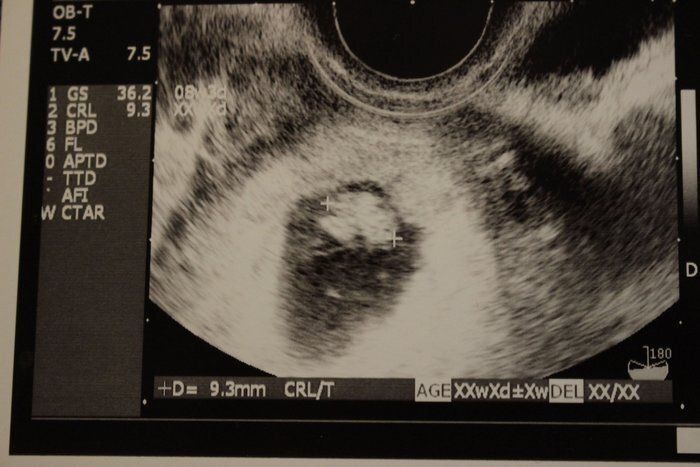

【妊娠6週】赤ちゃんのエコー写真・超音波写真まとめ

ママライターのみなさんの妊娠出産体験談から妊娠6週の赤ちゃんのエコー写真を集めました。

Tomomiさんの妊娠6週目のエコー写真 心拍確認できました

「ちゃんと大きくなっているかな?胎嚢の中に赤ちゃんは見えるかな?」不安な気持ちで内診台へ上がり、思わず手を組んで祈ってしまいました。先生のとっても嬉しそうな「おー、いたいた」という声にほっと胸を撫で下ろし、ピコピコ動くベビちゃん(胎児ネーム)の心拍を見ながら、「現実なのかな?」と信じられない気持ちでいっぱいでした。

私にとって4度目の妊娠陽性反応、そして初めての心拍確認!1つの大きな壁を乗り越えたと同時に、妊娠が継続するのかと、不安な気持ちと闘う日々も続くのでした…。